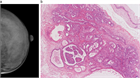

1. 30~40歳代の成熟期女性に好発する、硬結・腫瘤、疼痛、乳頭異常分泌などの症状を呈する乳腺の良性疾患である。

1. 癌との関係性は低いが、組織診で増殖性病変、特に異型上皮過形成が確認された場合、および乳癌家族歴(第1度近親者)がある場合は、癌になるリスクが高く、厳重な経過観察が必要である。(推奨度1)